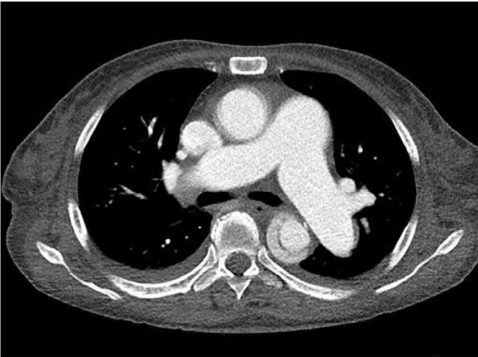

CT: Aortic dissection involving descending thoracic aorta

CT에서 descending aorta 내부의 free flap이 관찰되므로 AD로 진단한다.

• AD 진단을 위해 시행한 가슴 CTdescending aorta 내부의 free flap이 관찰되므로 AD로 확진한다.

CT: Intimal flap, false lumen